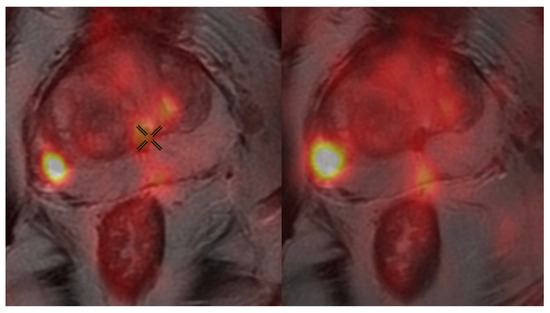

2.3. PSMA PET/CT Protocol

3.2. Impact of Uptake Period on SUVmax